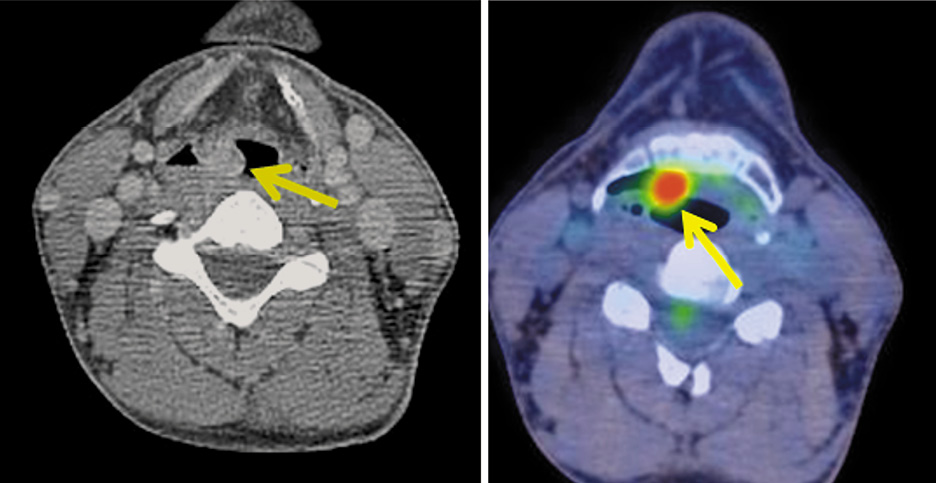

В черпало-надгортанной складке справа, широко прилегая к гортанной поверхности надгортанника, определяется полиповидное образование размером 11×14 мм, неоднородной структуры с гетерогенным контрастным усилением, коэффициент максимального накопления 18-ФДГ, SUVmax 1,15 (рис. 4).

Рис. 4. Больной С., 43 года. На аксиальной КТ- и совмещенной ПЭТ/КТ-проекциях в черпало-надгортанной складке справа определяется полиповидное образование размером 11×14 мм, SUVmax 11,15.